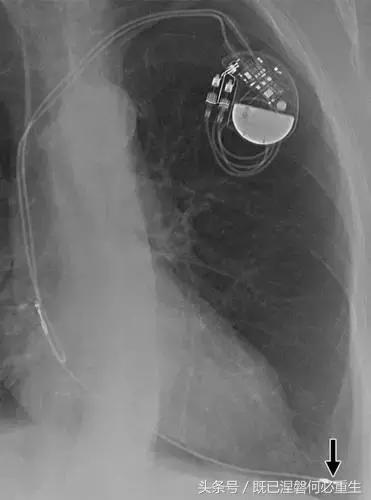

图。 6A 75岁的男性患有心房导线脱位。

A,Medtronic双腔起搏器的右心房导联(箭头)显示在正面(A)和外侧(B)图像上的纯垂直路线。 电极在心房中自由浮动。 患者抱怨经常心悸,并且设备检查显示不能可靠地去极化心房。 心房导线修订(未示出)导致心悸消除。 心房导线的推荐放置位于右心耳,但右心房中的导联可充分发挥作用。 在任一位置正确固定到壁上的引线通常将显示一定程度的曲率。

图。 6B 75岁的男性患有心房导线脱位。

B,Medtronic双腔起搏器的右心房导联(箭头)在正面(A)和侧面(B)图像上显示纯垂直路线。 铅在心房中自由浮动。 患者抱怨经常心悸,并且设备检查显示不能可靠地去极化心房。 心房导线修订(未示出)导致心悸消除。 心房导线的推荐放置位于右心耳,但右心房中的导联可充分发挥作用。 在任一位置正确固定到壁上的引线通常将显示一定程度的曲率。